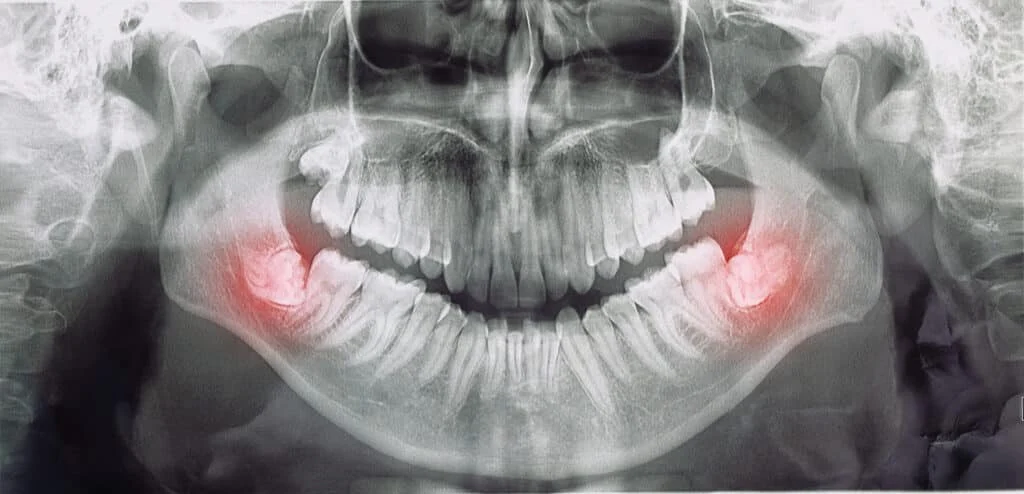

Wisdom teeth X-ray

Signs You May Need Your Wisdom Teeth Removed

Healthy, properly aligned wisdom teeth with room to grow rarely lead to problems. In most cases, wisdom teeth aren’t able to emerge correctly due to...